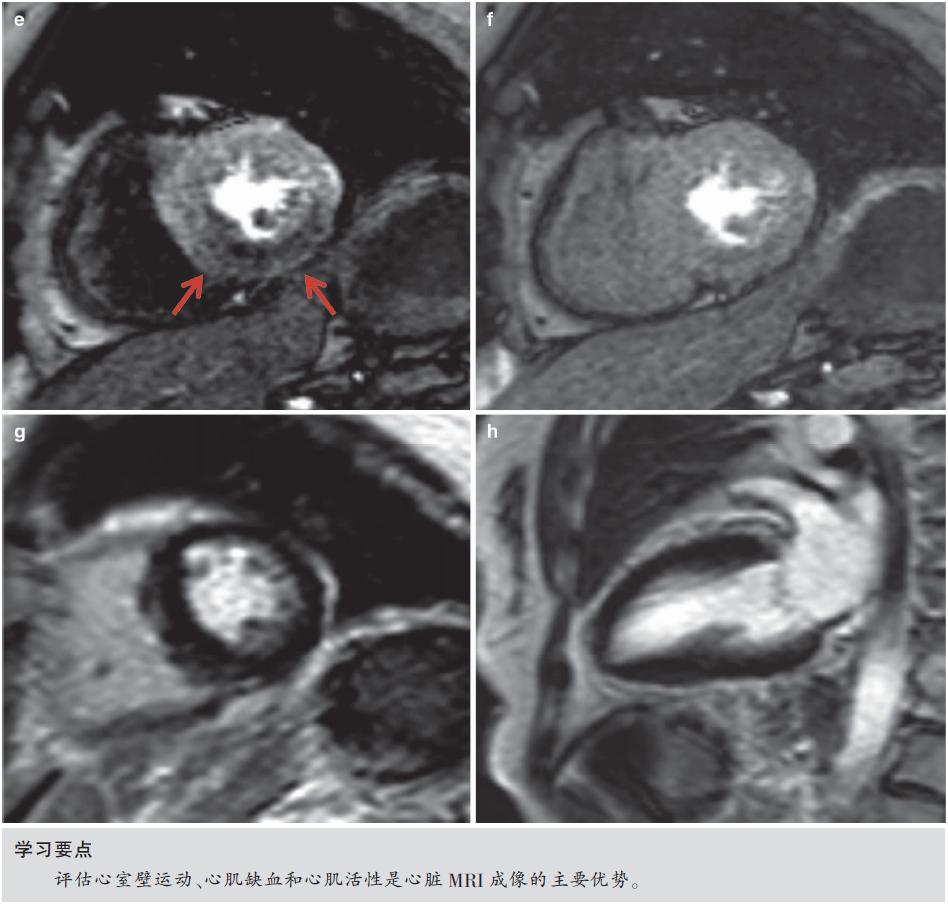

图7.5 心肌缺血,RCA明显狭窄。患者女性,82岁,胸痛。采用1.5T MR获得非对比增强的三维CMRA图像,采用稳态自由进动(SSFP)序列、导航回波门控、T2预扫描、光谱预饱和、反转恢复脂肪饱和(TR/TE,4.6/2.3ms;翻转角度,90°;SENSE因子4;FOV 280mm×280mm×120mm;采集矩阵256×256×80;重建矩阵512×512×160)。

(a)全心冠状动脉MR造影MIP图像显示RCA明显狭窄(箭头)。(b)冠状动脉MR造影与有创冠状动脉造影(箭头)之间存在良好的一致性。(c)舒张末期的短轴MR电影图像,(d)收缩期并不显示明显的区域性室壁运动异常。(e)负荷和(f)静息时心肌灌注MR图像显示下壁的严重缺血(箭头),与RCA供血区对应。(g,h)晚期钆增强MR图像未见心肌瘢痕。